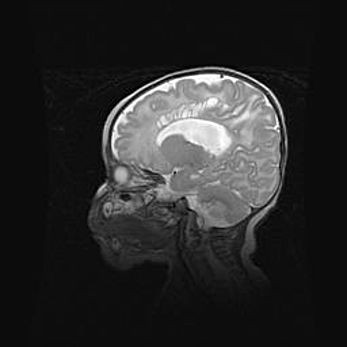

Аномалия Денди-Уокера. Признаки гипоплазии мозолистого тела.

Возраст: 5 месяцев 3 дня

Вес: 5550 г

Пол: мужской

Окружность головы: 39 см

Срок гестации: 40 недель

Аномалия Денди-Уокера – это порок развития головного мозга, для которого характерна триада симптомов: гипотрофия или аплазия червя мозжечка и/или полушарий мозжечка, расширение четвёртого желудочка с формированием ликворной кисты задней черепной ямки, гипертензионная гидроцефалия различной степени.

Гипоплазия мозолистого тела относится к дефектам внутриутробного этапа развития мозговой ткани, возникающим в процессе закладки структур головного мозга, что происходит на начальных этапах развития эмбриона.